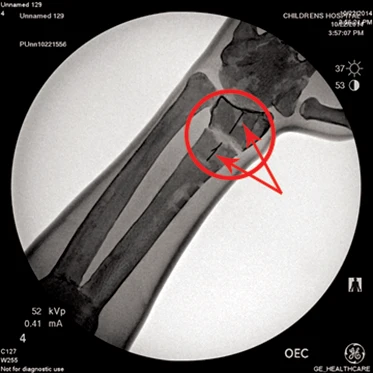

This multi-discipline trainer allows users to incorporate manual reduction with real time fluoroscopic visualization.

- Soft tissue arm model with radiopaque coated bones and a multi-position universal bed rail clamp allowing the user to train in the most common patient positions.

- Also includes an adapter plate for set up with a table mounted clamp, a video tutorial presented by the Children’s Hospital of Philadelphia, and an instructor’s guide on lesson plan proficiency goals and instructor training tips.

- The tactile hands-on feel and real-time imagery enhance the user experience. The reduction model allows palpation of internal structures through the soft tissue before and during reduction.

- The radius bone has alignment guide lines to allow the user to assess the accuracy of the reduction after cast application. Casting materials can be removed using standard cast removal techniques.